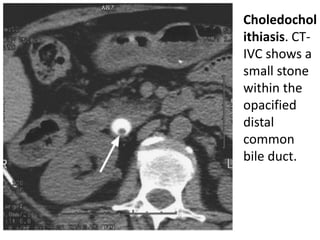

• Choledochol

ithiasis. CT-IVC

shows a

small stone

within the

opacified

distal

common

bile duct.

• Choledochol ithiasis.CT-IVC shows a small stone within the opacified distal common bile duct.